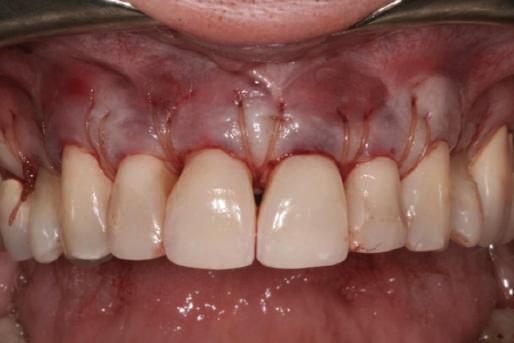

Figurile

20. Dintele 1.1. tratat endodontic.

21. Dintele 1.1. submersat în cele din urmă după inserarea bontului la nivel 1.2. şi 2.1.

22. Os excelent vestibular faţă de toate implanturile; nicio recesie la nivelul 1.3. şi 2.3. 23. Punte provizorie pe toate bonturile.

matică sau inflamatorie, în timp ce un biotip subţire este mai susceptibil la recesie periimplantară indusă de resorbţia peretelui cortical vestibular subţire (Saadoun, Touati). De aceea, în cazul celor din urmă, cu grosimea gingivală vestibulară sub 1,5mm, se recomandă ca implanturile să se plaseze mai palatinal şi apical (Bashutski, Wang). Saadoun & Touati sugerează că o grefă de ţesut conjunctiv transformă un biotip subţire într-un biotip gingival gros, care în cele din urmă consolidează stabilitatea gingivală şi îmbunătăţeşte managementul tisular pe toată durata fazei restauratorii. Grefarea minoră pentru îmbunătăţirea nivelului de ţesut cheratinizat ataşat a fost implicată în cazurile 3 şi 6.